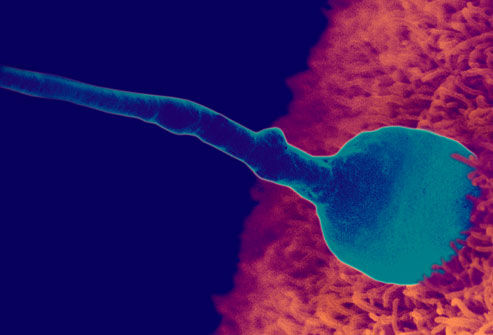

现在小编将整理出的胎儿发育图呈现给大家: